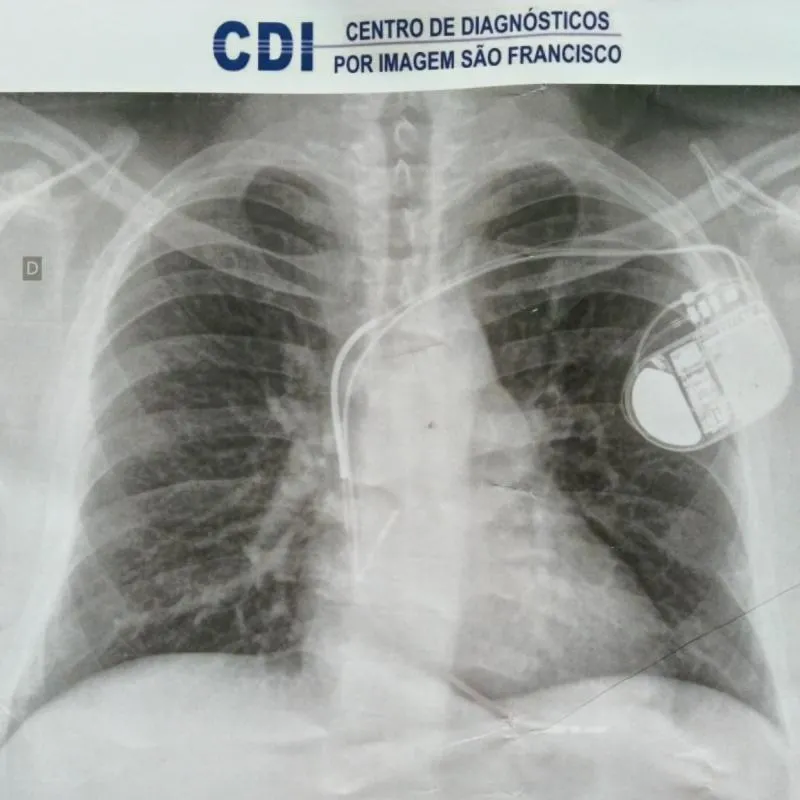

O Leandro é portador de uma doença rara chamada Displasia Arritomogênica do Ventrículo Direito (DAVD). Trata-se de uma doença hereditária que compromete o ventrículo direito de forma progressiva. O tratamento consiste num implante de um Cardioversor Desfibrilador Implantável (CDI), um aparelho que leva eletrodos no coração e que emite choques em diferentes níveis caso o coração fibrile ou pare de funcionar. Basicamente é o que mantém ele vivo caso tenha uma parada cardíaca.

Atualmente, ele tem o aparelho que colocou em 2016, que está em 9% de bateria, necessitando de troca o mais rápido possível. Estima-se que em dois meses a bateria do aparelho atinja os 6% (carga reserva) e algumas funções importantes deixem de funcionar. Por isso, é fundamental ele fazer a troca desse aparelho para manter a qualidade de vida, e é por isso que essa rifa foi criada, para ajudar com todos os custos da cirurgia que não é simples de conseguir pelo SUS.

CID I-50 Insuficiência cardíaca

CID Z-950 Presença de marca-passo cardíaco (não existe CID específico para quem tem CDI)

O QUE É E COMO FUNCIONA O CDI?

O desfibrilador implantável foi desenvolvido para monitorar o ritmo cardíaco 24 horas por dia. Se o coração está batendo muito rápido ou de forma irregular, o dispositivo envia primeiro pequenos sinais elétricos indolores para corrigir o ritmo cardíaco. Se o ritmo cardíaco continuar acelerado, o desfibrilador aplica um choque para trazer o ritmo cardíaco de volta ao normal, é isso que mantém a pessoa viva caso ela sofra uma fibrilação.

É importante ressaltar que o CDI NÃO É um marcapasso, apesar de ter a função marcapasso nele!